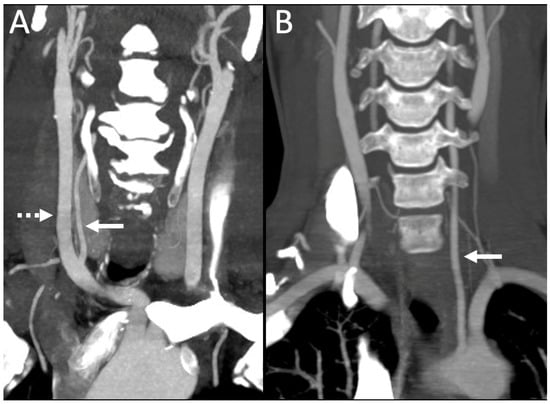

3.3. Vertebral Artery Dominance (VAD)